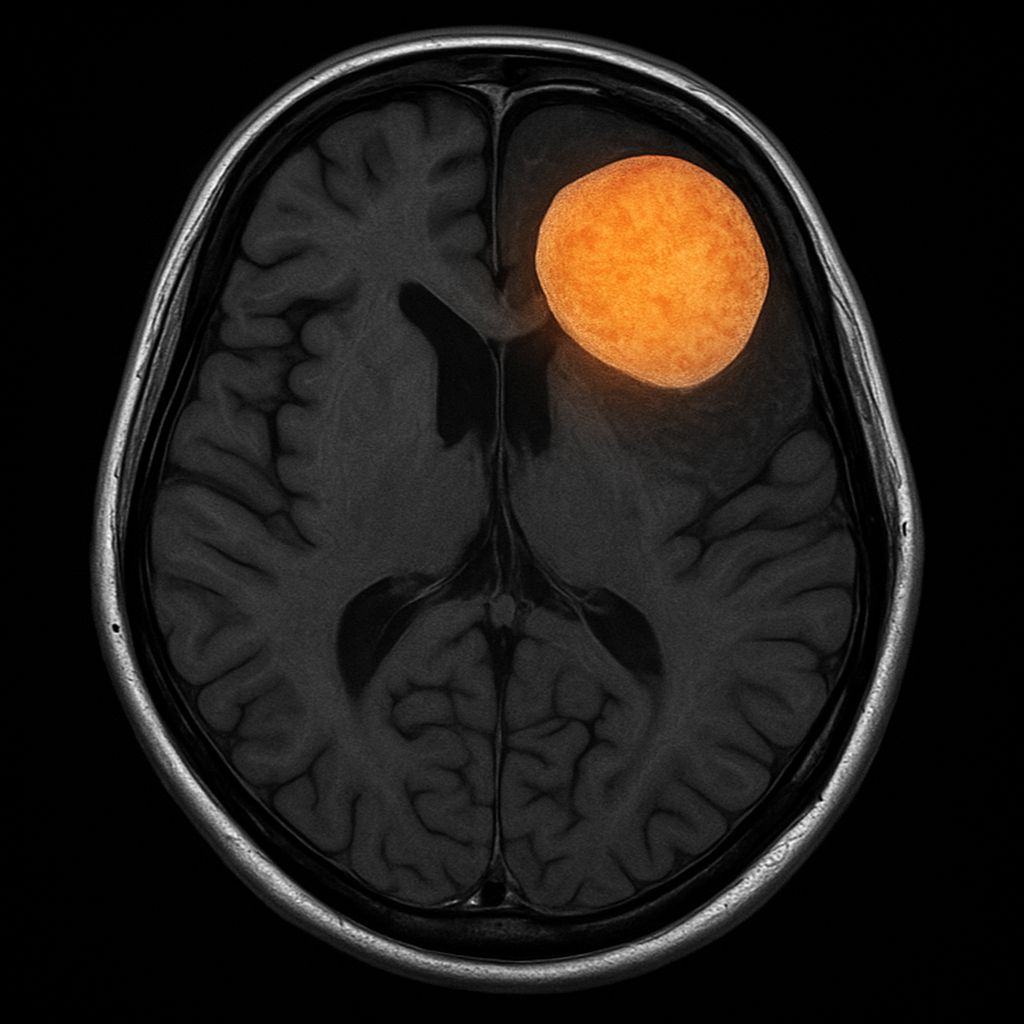

• Diagnosis is clinical, supported by characteristic MRI findings of large, bilateral, asymmetric T2/FLAIR hyperintense lesions without mass effect.

• Lesions are poorly demarcated, often involve both gray and white matter, and rarely show gadolinium enhancement.